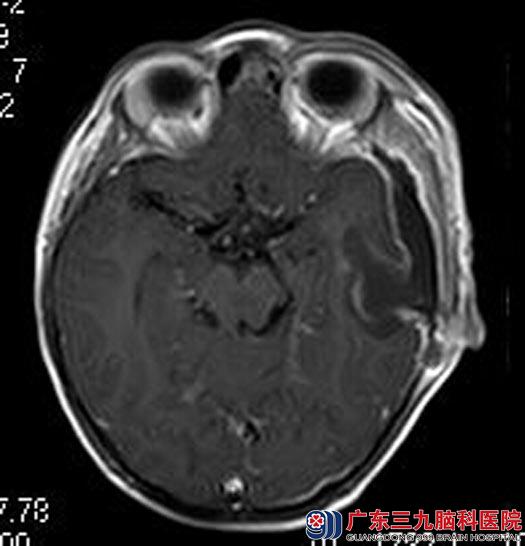

鲁明主任建议行手术治疗,经家人同意后,在全麻下行左侧颞部中颅窝底占位切除术,术中显微镜下见中颅窝底白色肿瘤组织,质硬、血供丰富,边界清晰,肿瘤基底位于颅底硬膜,沿颅底硬膜向下切断肿瘤基底并止血,再沿肿瘤周边分离分块全切肿瘤,手术顺利。术后豆豆食欲明显好转,已康复出院。术后病理结果:神经纤维瘤。

手术后